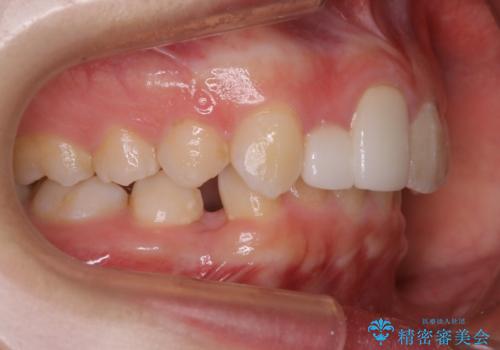

- 前歯の並びを気にして来院。

右上の2番目の前歯のセラミックが小さく、並びが気になるとのことでした。

右上の2番目の前歯が奥に入っている状態で、かぶせてあったため左に比べて短いセラミックになってしまっていました。